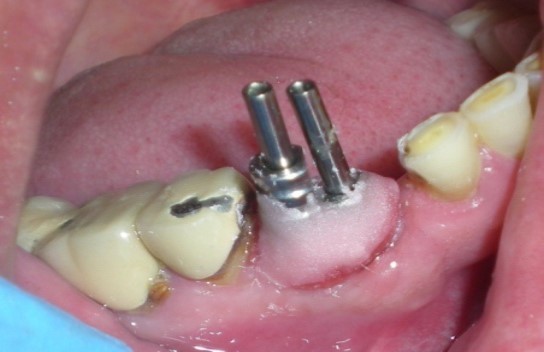

Insufficient space between two impression copings, preclude the flow of impression material between them, which may lead to movement of the impression coping resulting in an inaccurate impression. To overcome this, the two impression copings were connected with auto polymerizing acrylic resin (Figure 4, Rapid Repair acrylic resin. DPI, India)

Figure 4.Modified impression copings splinted with unmodified coping with autopolymerizing acrylic resin.